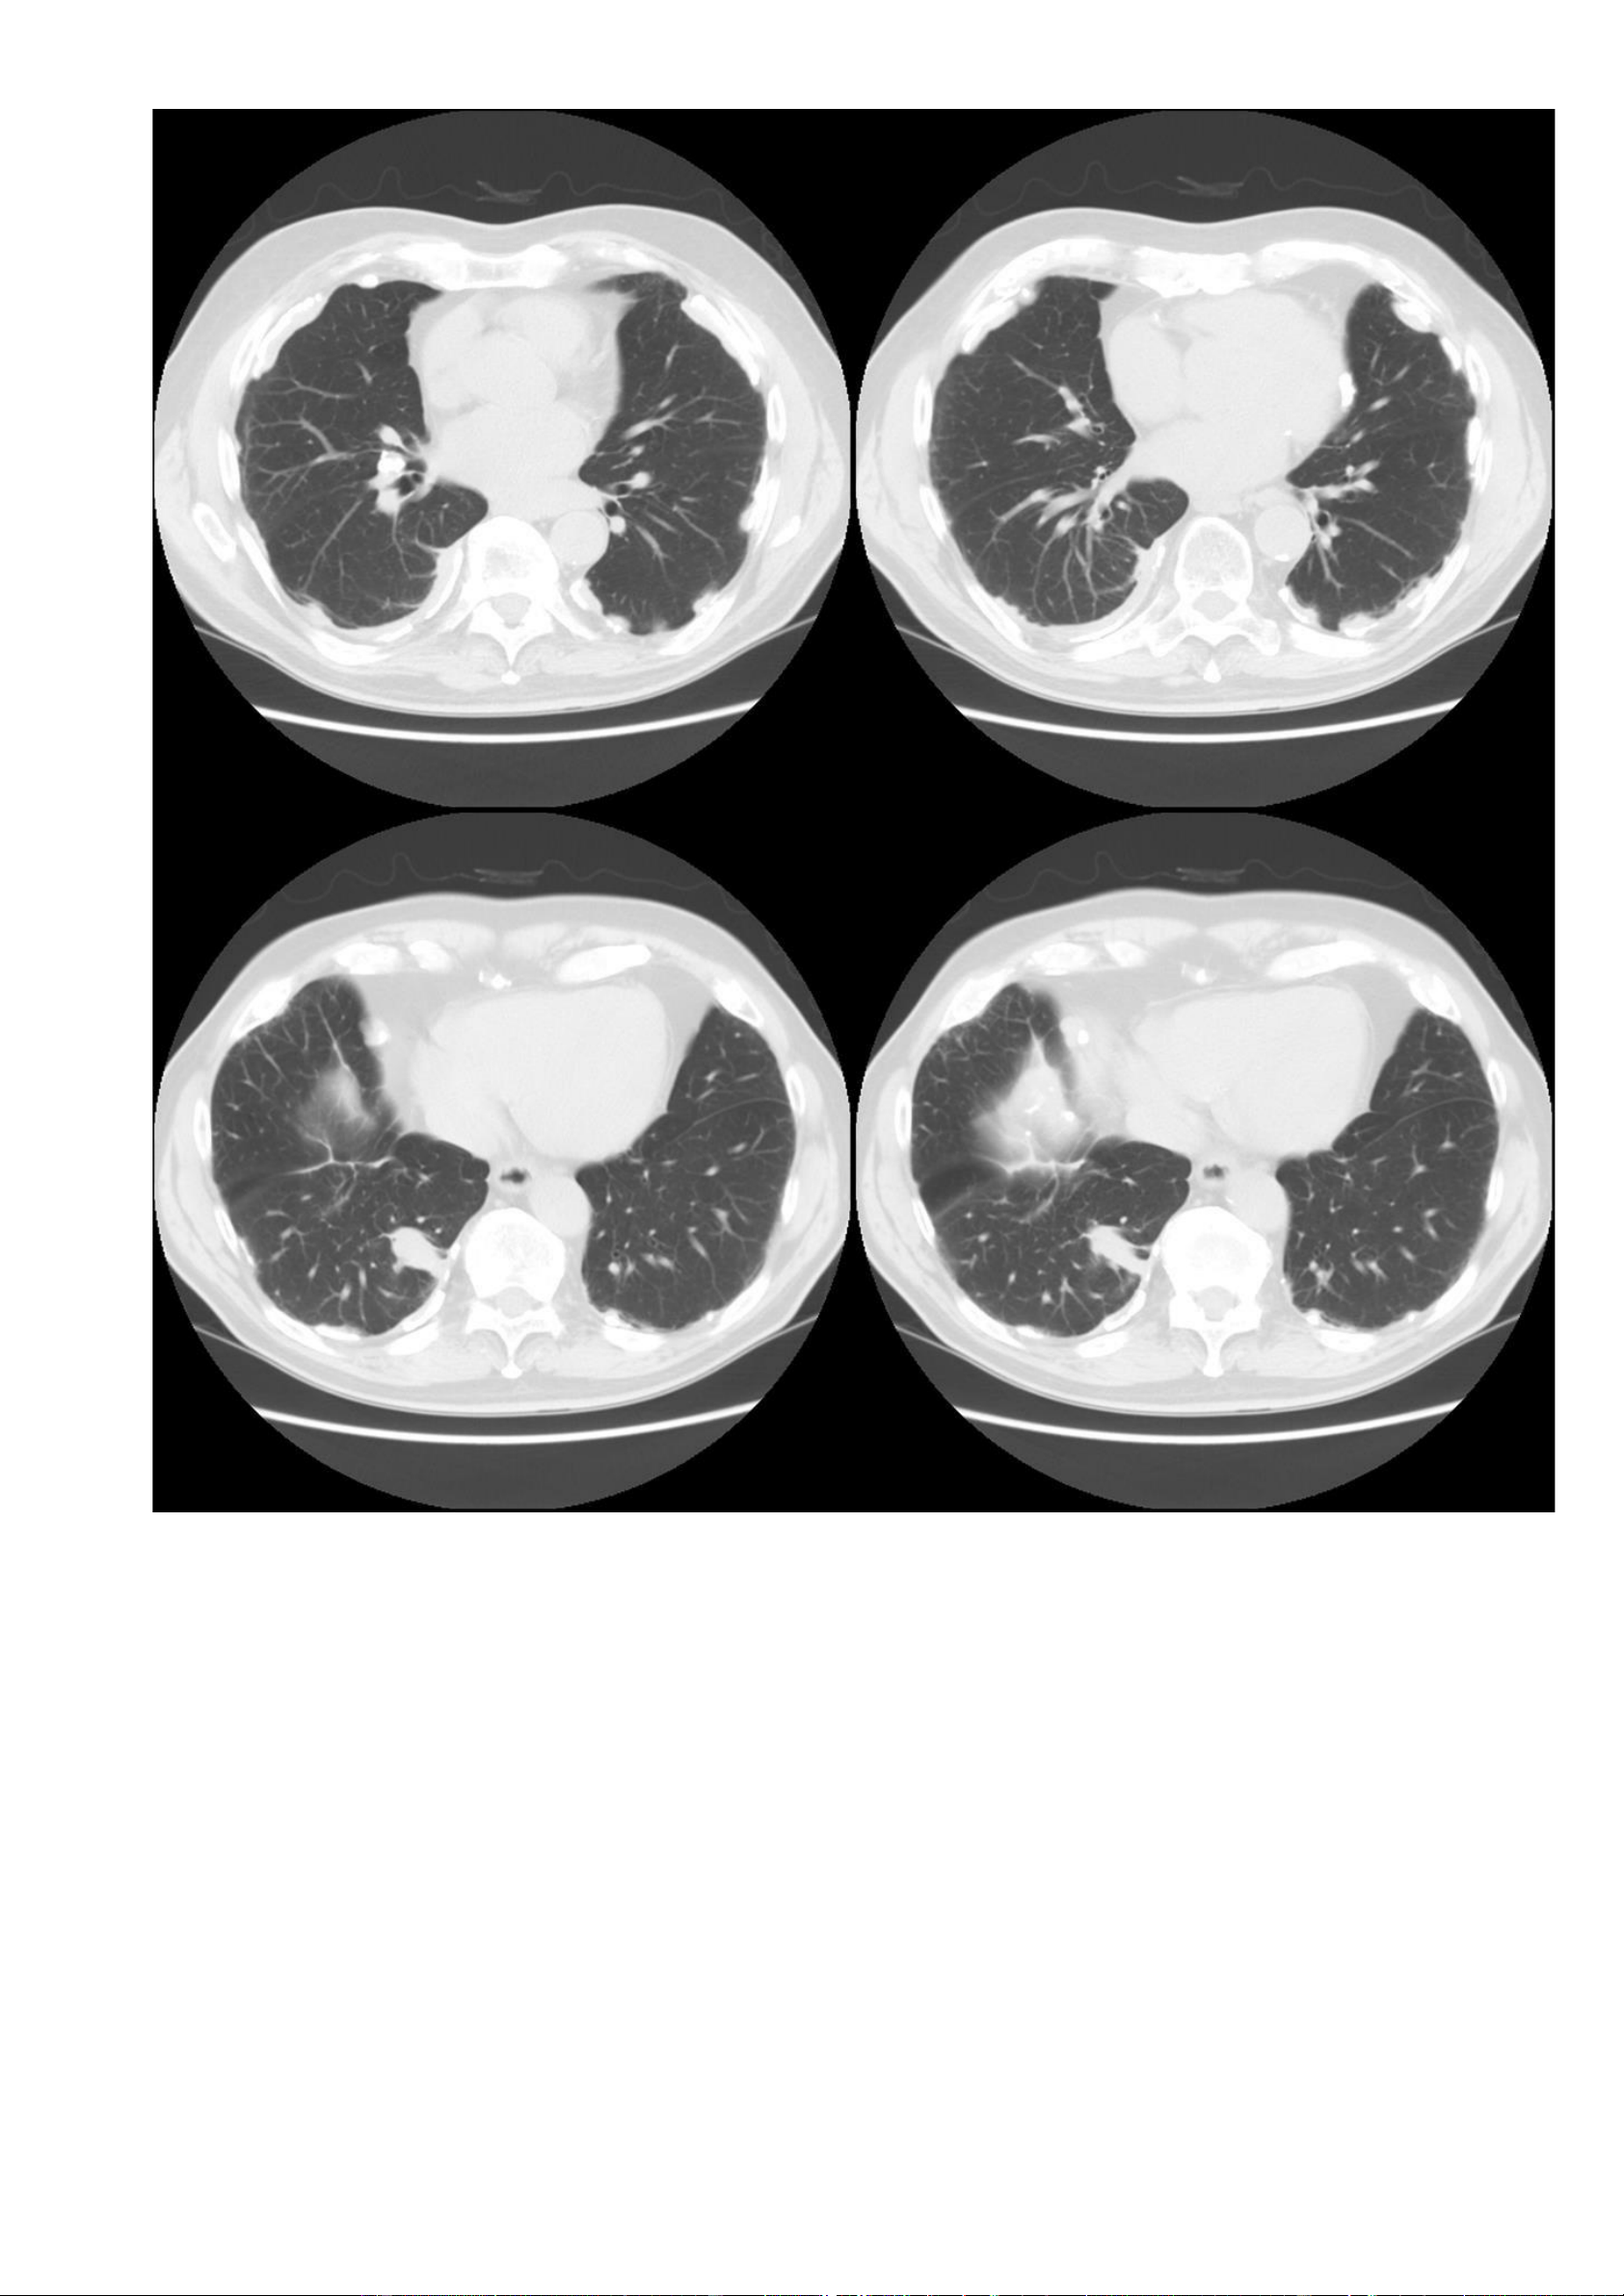

Nguồn link: https://radiopaedia.org/cases/asbestosis - Thông tin bệnh nhân: Không có. - Hình ảnh CT: + Cửa sổ nhu mô: lOMoAR cPSD| 22014077 Phan Tùng Bách

▪ Một vài dải nhu mô dưới màng phổi hai bên.

▪ Sẹo vùng đỉnh phổi hai bên.

+ Cửa sổ trung thất – không tiêm thuốc cản quang: lOMoAR cPSD| 22014077 Phan Tùng Bách

▪ Ghi nhận các mảng màng phổi hai bên.

▪ Không có tràn dịch màng phổi (pleural effusion), không có hạch to. -

Các dấu hiệu trên cửa sổ nhu mô và cửa sổ trung thất, phù hợp với bệnh phổi-màng phổi liên quan đến amiăng. 7.3. Trường hợp 3: -